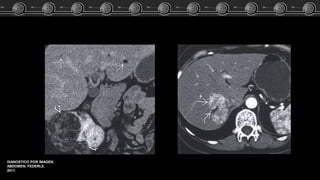

Fem de 83 años…. El estudio TC demostró lesión focal a nivel del lóbulo

izquierdo del higado.

ARCHIVO DOCENTE DE

TOMOGRAFÍA Y

RESONANCIA C.M.C.

Adenoma, Hemangioma ó HNF?? Caso Clínico